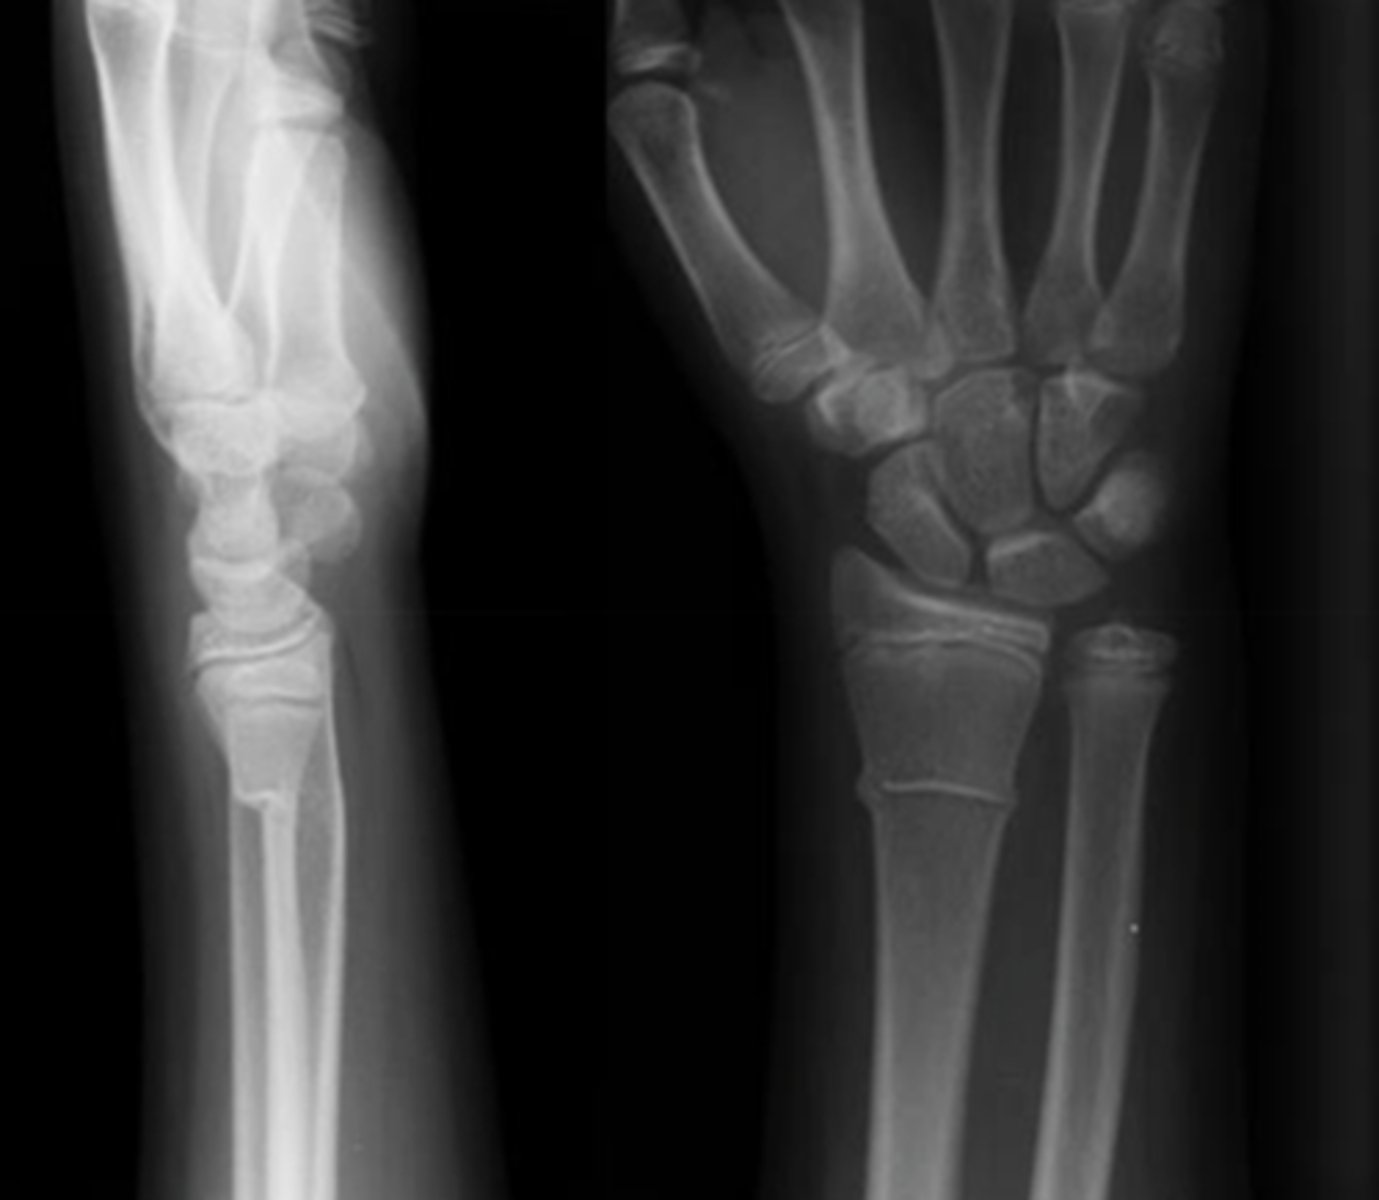

Fracture of distal radius with posterior displacement

Colles' fx

Fracture of distal radius with anterior displacement

Smith's fx